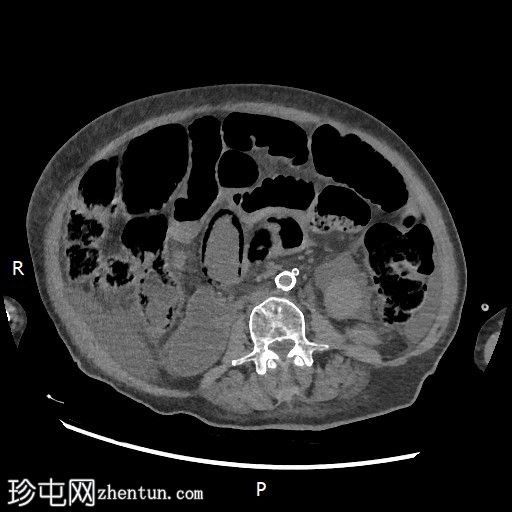

CT

轴位增强扫描(门静脉期)

大肠内可见中度粪便。横结肠轻度扩张(约6.6厘米)。

数处小肠袢直径接近临界值(约3厘米),部分肠袢内可见粪便。

腹部中央及右侧可见数处小肠袢肠壁明显变薄,并可见肠壁积气。

少量腹水。

主动脉及其内脏分支可见明显动脉粥样硬化。肠系膜上动脉(SMA)开口处中度至重度狭窄;但开口后显影良好。

目前未见明显的门静脉-肠系膜静脉积气。

无气腹。